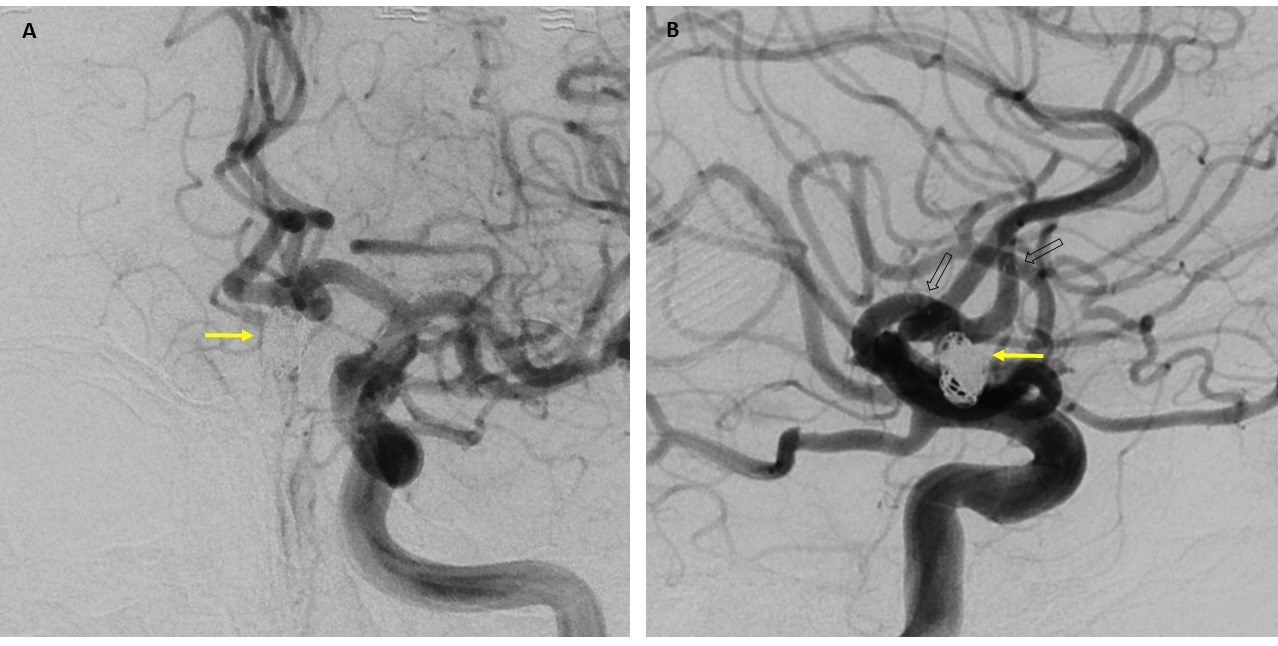

Imagen 4: Proyecciones anteroposterior y lateral oblicuas en nativo de fluoroscopia tras la liberación del stent (A y B) y tras el intento de microcateterización del segmento A2 derecho para “stenting en Y” (C y D). Obsérvese el acortamiento del extremo proximal del stent (flechas) tras intentar atravesar el mismo con el microcatéter.

Imagen 5: Capturas de fluoroscopia en nativo sin contraste intravenoso en proyecciones AP (imagen A) y lateral de cráneo (imagen B) que muestran resultado final de saco aneurismático relleno de coils (flecha amarilla) y posición respectiva del stent (flecha hueca indica patillas distales y cabeza de flecha las proximales).

Imagen 6: Resultado angiográfico en proyecciones AP (imagen A) y lateral de cráneo (imagen B) que muestran adecuada protección del saco aneurismático rellenado con coils y mínimo paso de contraste a su interior, así como ausencia de estenosis en el segmento arterial con stent liberado.

Desplegado el stent, se procede a cateterizar el segmento A2 derecho con catéter Excelsior SL-10 para realizar técnica “stenting en Y”, pudiendo ascender la microguía atravesando las celdas del stent, pero no así el microcatéter. No obstante, el intento de atravesar el stent con el microcatéter implicó un leve acortamiento de su extremo proximal que consiguió una mejor adaptación del mismo al cuello aneurismático consiguiendo una posición segura para proceder a la embolización del saco sin necesidad de desplegar el segundo stent (imagen 4).

Finalmente, se finaliza el procedimiento embolizando el saco aneurismático mediante la liberación de un total de 11 coils obteniendo un excelente resultado angiográfico con exclusión completa del aneurisma de la circulación (imágenes 5 y 6).